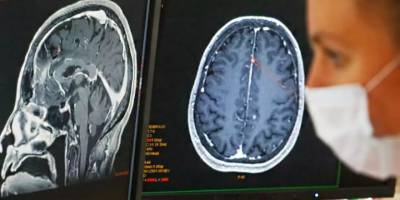

Sosyal eşitsizliğin fazla olduğu ülkelerde yaşayanların beyni daha hızlı yaşlanıyorSosyal eşitsizliğin fazla olduğu ülkelerde yaşayanların beyni daha hızlı yaşlanıyorAraştırma, sağlıklı bireyler ile Alzheimer gibi nörolojik rahatsızlıkları bulunan kişilerin beyin yaşları arasındaki farkları ölçtü.